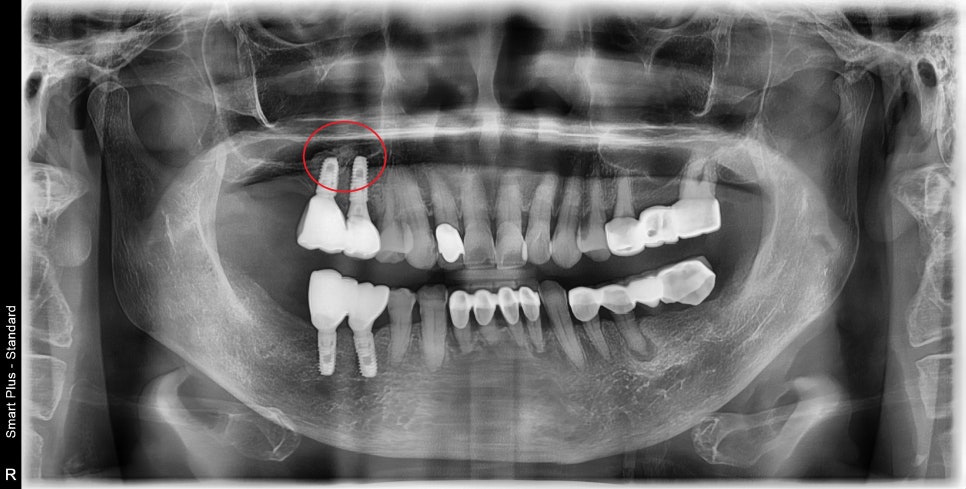

한쪽이 끝난 후..

그쪽으로 음식물이 빠지는 것 같고

씹히는 게 어색하고 안되는 거 같아요.

아무래도 어금니 하나가 없다 보니

전보다는 씹는 것이 조금 불편할 수 있습니다.

시간이 지나면서 점차 적응하시고

이제 식사도 잘 하시지만

반대쪽은 맨 끝 어금니까지 다 하고 싶다고 하셨습니다.